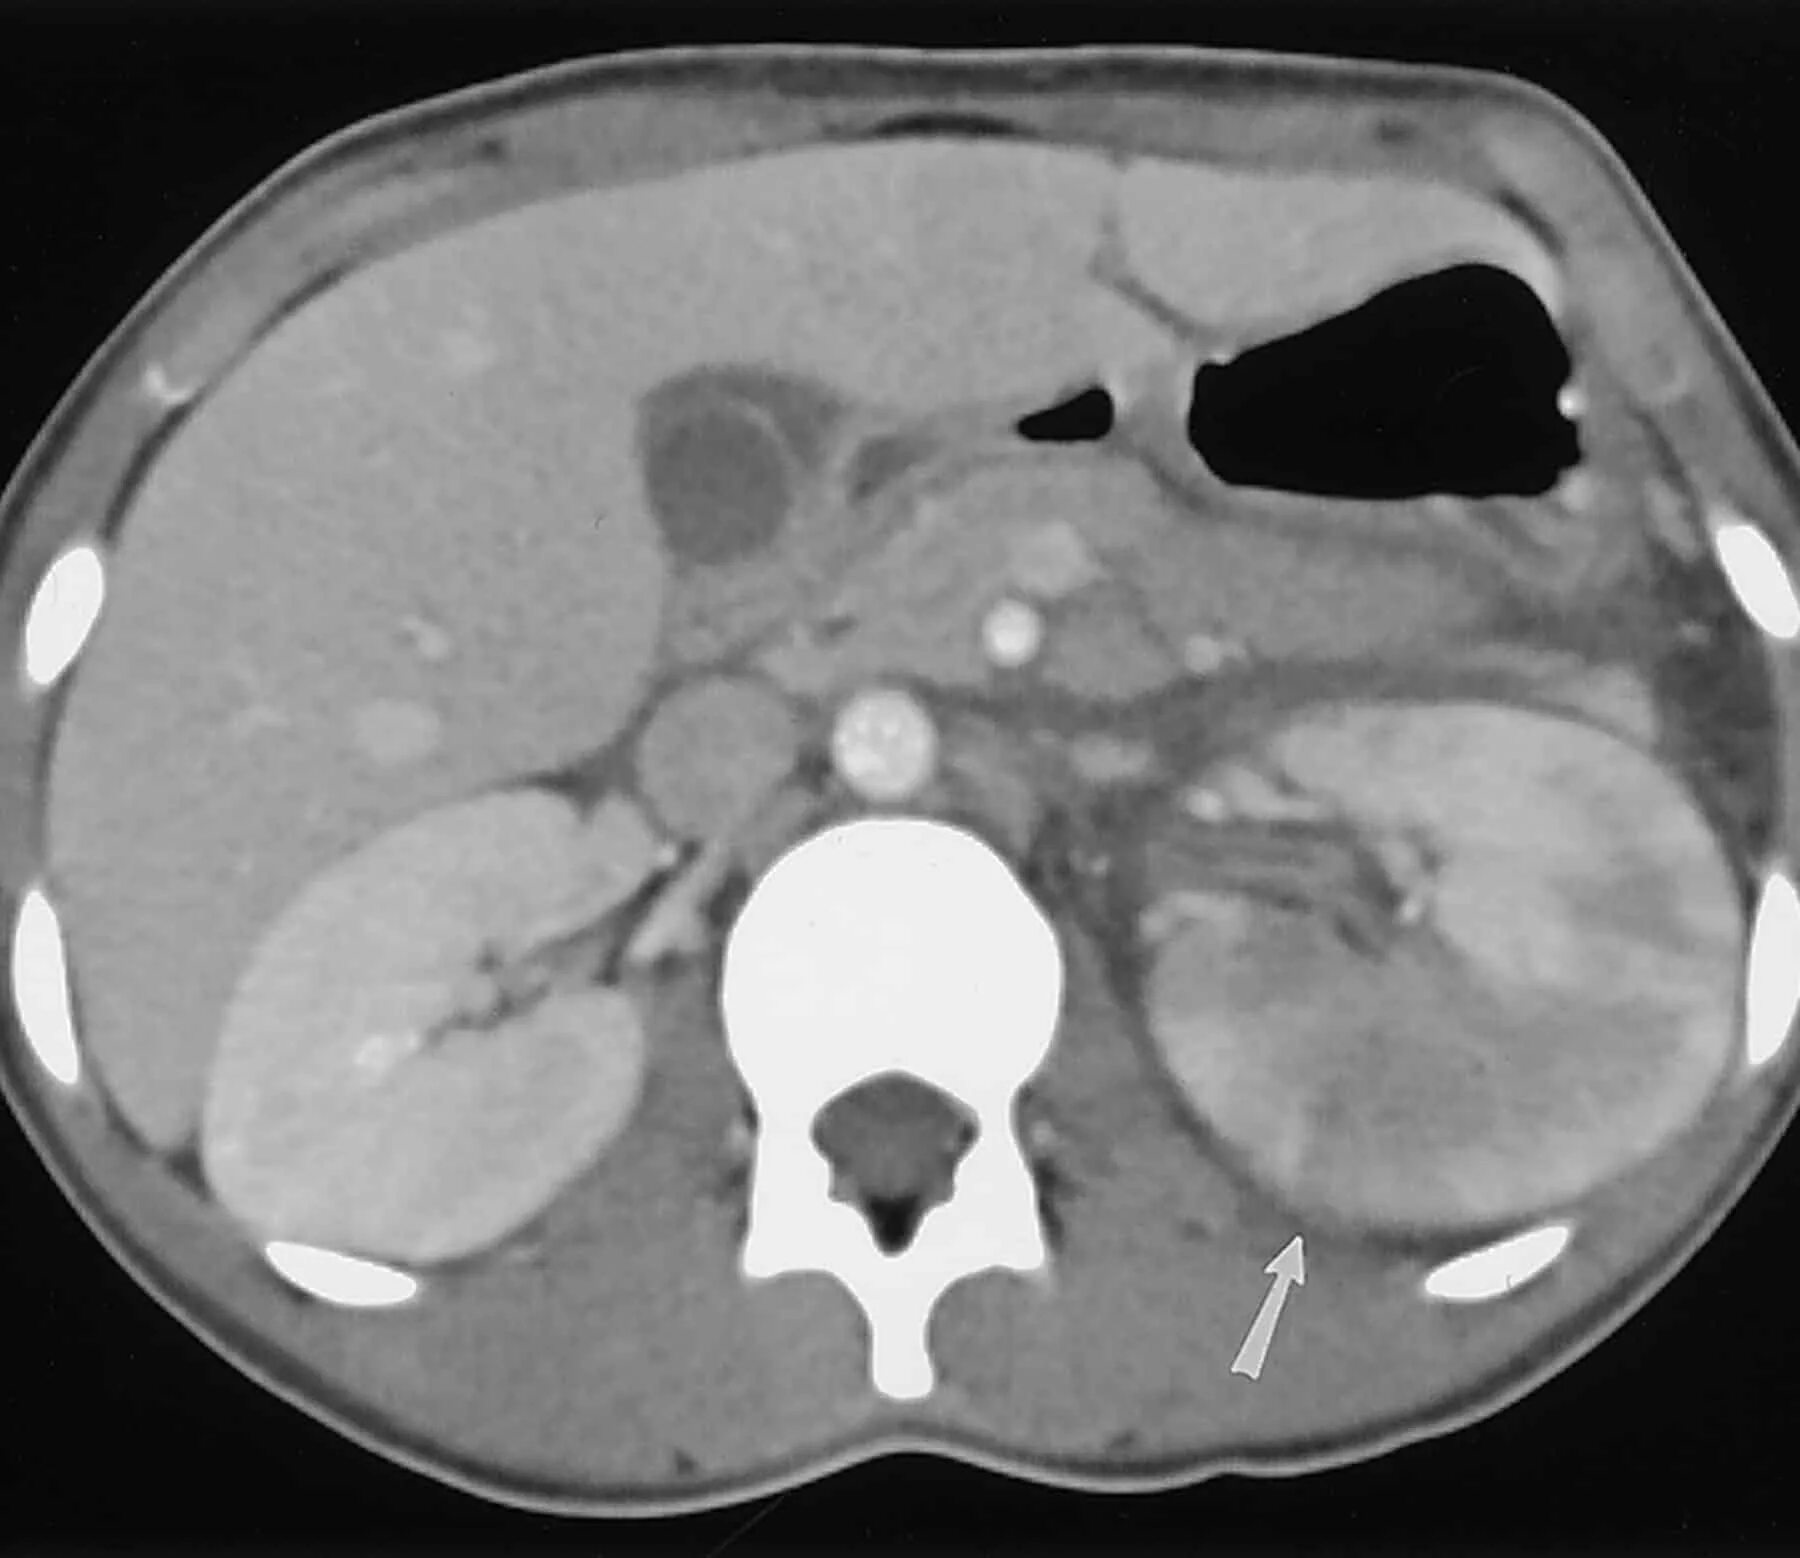

Пиелонефрит кт